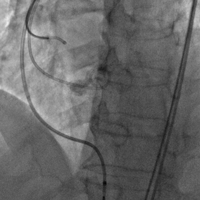

上午11时许,手术直播开始。手术经股动脉入路,使用23#预扩球囊进行跨瓣预扩,预扩后患者突发室颤,血压下降,考虑与患者心功能较差,预扩后反流增加有关。手术团队具有丰富经验,临危不乱,立即予患者电复律、心肺复苏,同时迅速为患者植入一枚25#Renatus介入主动脉瓣,以保证患者左心室-主动脉单向血流。瓣膜植入后,予以补液、血管活性药物治疗,患者血流动力学逐渐稳定,生命体征恢复平稳,术后超声及造影示:瓣膜位置理想,无瓣中返流及瓣周漏,TEE提示主动脉瓣平均跨瓣压差由术前38mmHg降至5mmHg,峰值流速由术前4.3m/s降至1.8m/s。整个手术在一小时内结束,最终获得成功。

术前造影 术后造影